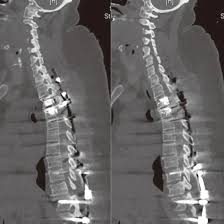

NCCT Lumbar Spine

Are you looking for an affordable NCCT Lumbar Spine scan? Medifyhome offers competitively priced MRI and CT scans, partnering with top NABL-certified diagnostic centres and clinics. Our facilities ensure high-quality imaging and accurate results. A Non-Contrast Computed Tomography (NCCT) of the lumbar spine is an imaging test that provides detailed cross-sectional views of the lower back without using contrast dye. It’s primarily used to detect fractures, assess degenerative changes, and identify conditions like herniated discs or spinal stenosis. NCCT scans are useful in evaluating trauma and lower back pain, especially when an MRI isn’t suitable. Since it doesn’t involve contrast, it’s safer for patients with kidney issues or contrast allergies. The scan is often performed quickly, allowing for prompt diagnosis and treatment planning for lumbar spine issues. To book an appointment for an NCCT Lumbar Spine scan, visit our platform, Medifyhome, or contact us at +919100907036 or +919100907622 for reasonable prices.